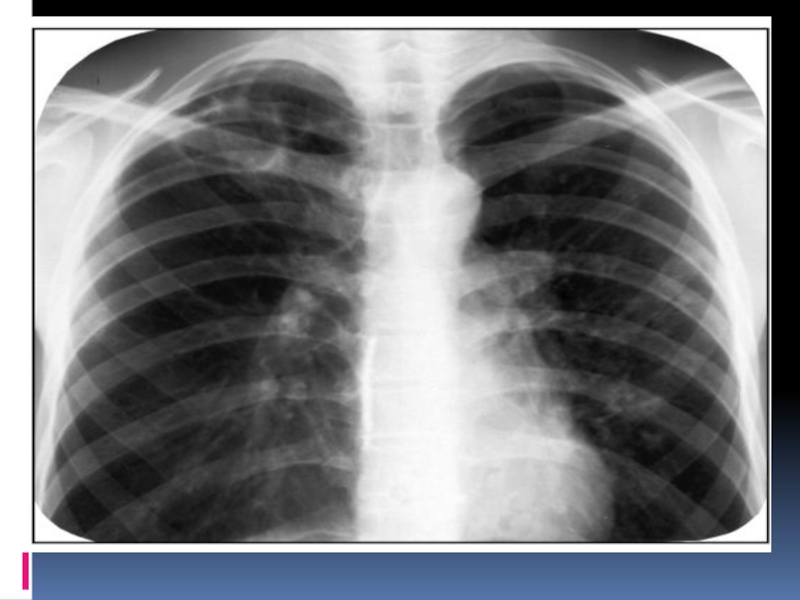

Кавернаның негізгі рентгенологиялық белгісі перпендикулярлы проекцияда сақталатын тұйық сақина тәрізді көлеңке

болып табылады.

Сақина тәрізді көлеңкемен шектелген өкпе бөлігі кавернаның терезесі деп аталады. Айналасындағы өкпе тініне қарағанда, ол мөлдірлеу болады. Өкпенің элементтері негізделген құрылымдарында кавернаның терезесінде көлеңкелер көрінбейді